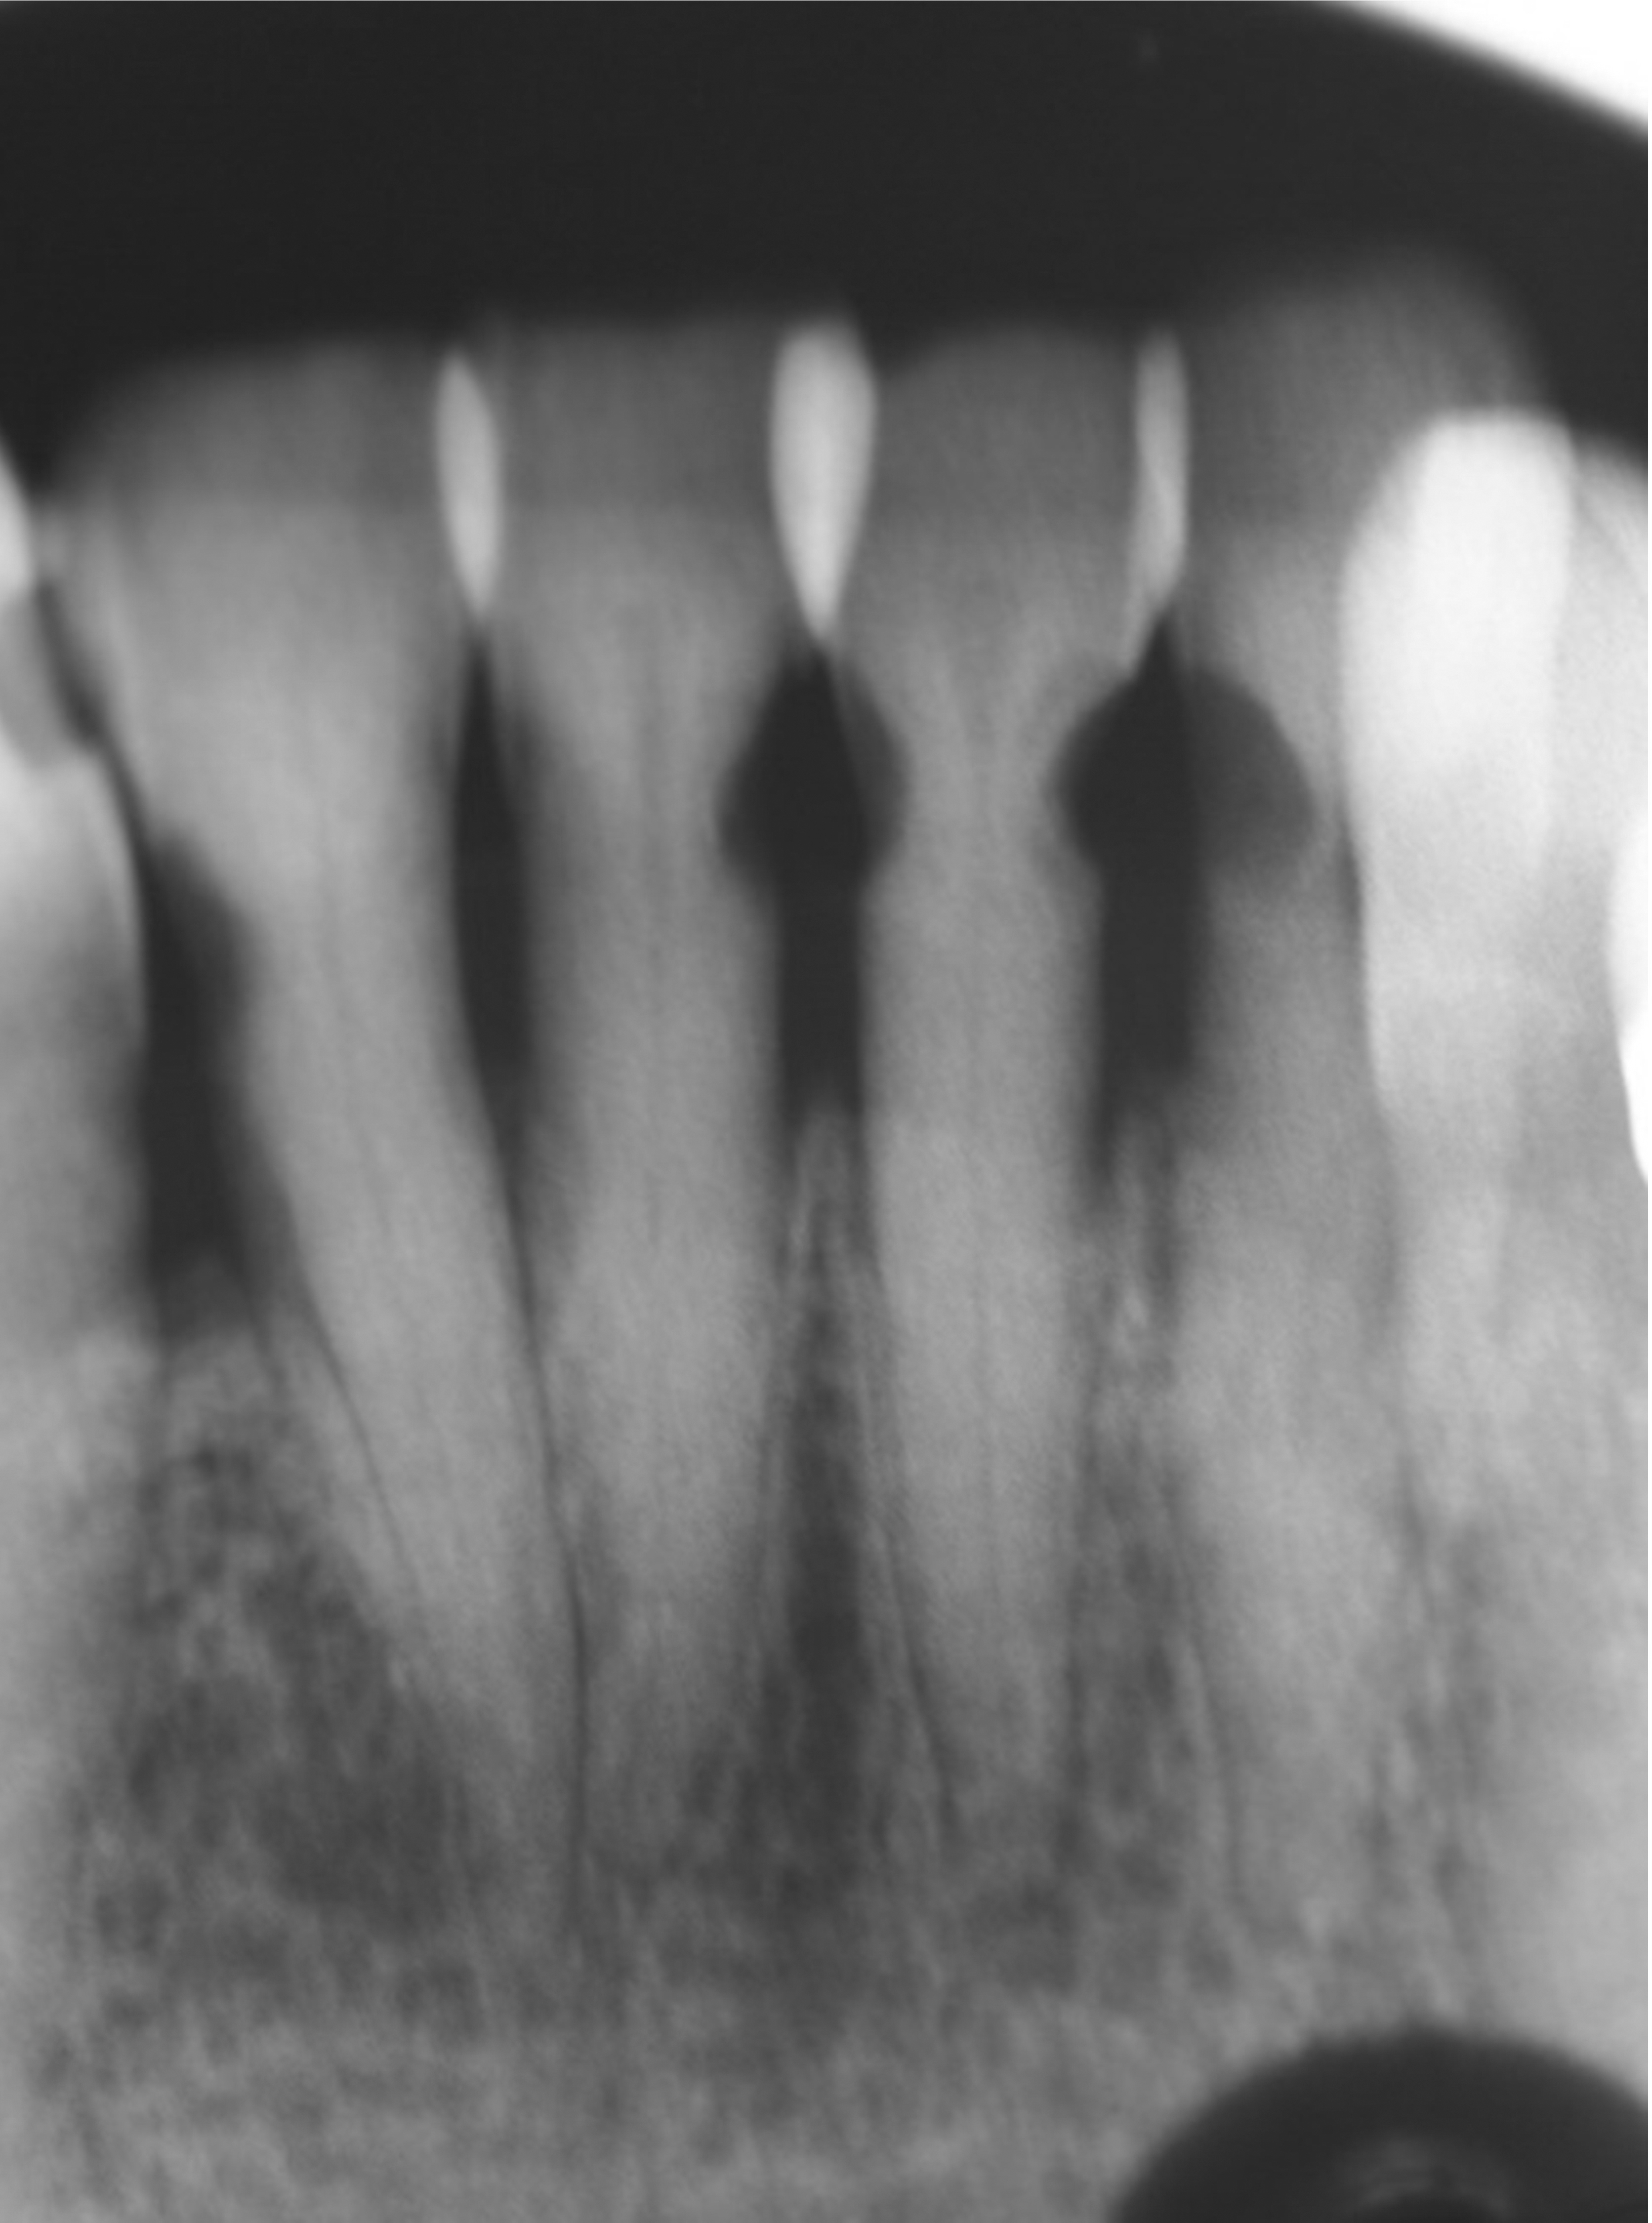

Fig 7. The lower incisors were responsive to electric pulp testing with no radiographic pathology.

Figure 7